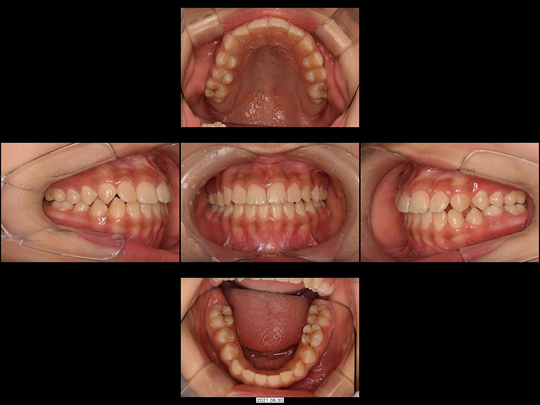

矯正後

画像をクリックで拡大

治療の説明

上の前歯2本が生えてこないのを心配しておられたのに、「様子見しましょう」とずっと言われ続けてお困りでした。中には「大学病院でしか対応できません」と言われたこともあったようです。

CT検査の結果、歯が歯ぐきの中に埋まった埋伏(まいふく)といわれる状態でした。歯ぐきだけでなくあごの骨まで歯に被さっていたため、埋伏している前歯の表面を傷つけずにあごの骨まで削り、引っ張り出すための外科処置(外科的開窓牽引による矯正)を行いました。奥歯の乳歯から永久歯への生え変わりのスペースもないので、あわせてあごの骨も拡大しています。

治療の期間・回数

40か月、40回

​費用

541,000円

リスクや副作用:出血を伴う可能性があります。治療後に、痛みや腫れ、出血を引き起こす可能性があります。

装置に慣れるまでに1週間ほどかかる可能性があります。歯列を広げる過程で少し痛みを感じる可能性があります。装着時に多少しゃべりづらくなる可能性があります(2~3週間ほどで慣れます)。